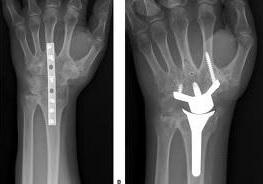

In de meeste gevallen blijft een deel van het kraakbeen (de glij-oppervlakken van het gewricht) gespaard. Door alleen de versleten glij-oppervlakken weg te nemen en/of vast te zetten wordt de pijn verbeterd. Omdat de goede glij-oppervlakken worden gespaard behoudt de patiënt toch nog enige polsbeweeglijkheid. De meest gebruikte operatietechniek is de 'scafoidectomie en 4 corner fusie'. Deze operatie bestaat erin het scafoid-beentje weg te nemen en 4 andere beentjes te laten vastgroeien.

Gemiddeld heeft een patiënt na deze ingreep een duidelijke verbetering van de pijn, blijft 45% van de normale polsbeweeglijkheid bewaard, en is er een verbetering van de kracht van 41% naar 80% van de andere zijde.

Indien het volledige polsgewricht versleten is, dient het volledige polsgewricht te worden vastgezet om de pijn de verbeteren. Alhoewel de pols niet meer beweegt, blijft de patiënt wel in staat met de onderarm te draaien en met de vingers te bewegen. Ook zware belasting blijft mogelijk.

In uitzonderlijke gevallen kan worden gekozen voor een bewegingssparende polsprothese. Na deze ingreep dient de belasting wel te worden beperkt om vroegtijdige slijtage of loslating van de prothese te voorkomen.